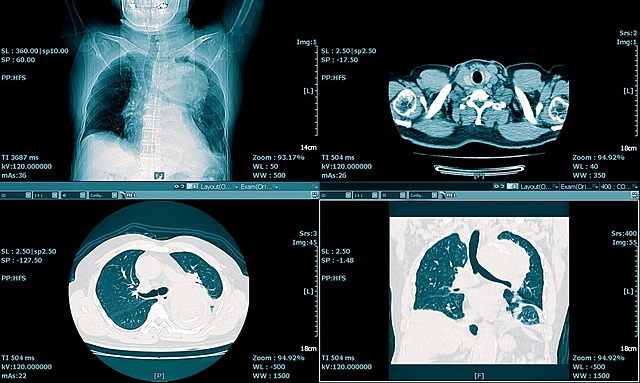

• Invention of CT Scan

Invention of CT Scan

In 1972, a man named Godfrey Hounsfield created the CT scan using x-rays which creates cross-sectional imaging. He was eventually awarded the Nobel peace prize for his contributions to medicine.